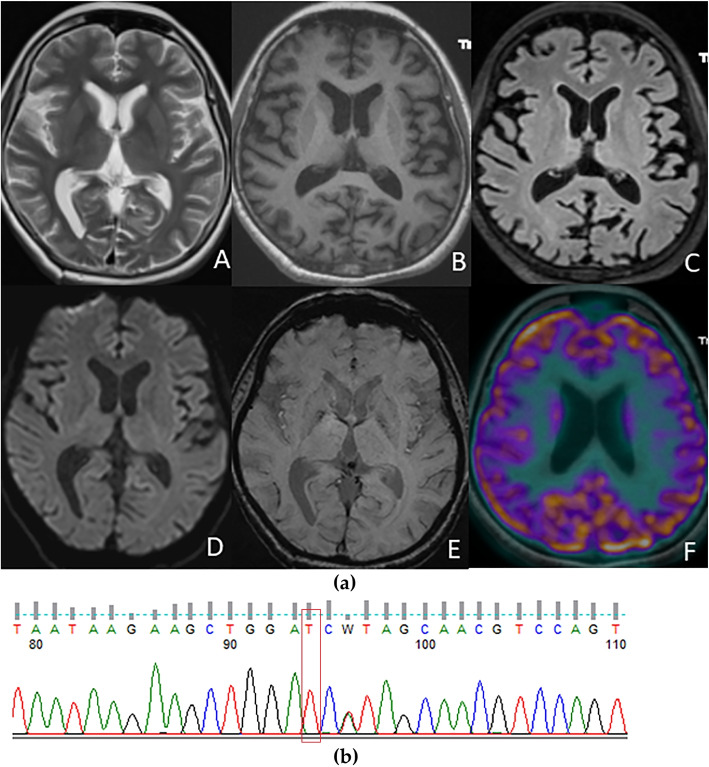

背景/目的:额颞叶痴呆(FTD)是早发性退行性痴呆的常见病因之一,是一种临床和病理异质性的神经退行性疾病。在全球范围内,微管相关蛋白Tau (MAPT)、前颗粒蛋白(GRN)和9号染色体开放阅读框72(C9orf72)是常见的FTD基因突变。然而,在印度还没有报道,到目前为止,只有一种前颗粒蛋白(PGRN)突变被报道。本研究旨在首次使用全外显子组测序(WES)描述来自印度额颞叶痴呆队列的7例FTD患者携带致病性MAPT突变的临床特征和放射学模式。方法:从南印度一所教学大学医院招募符合额颞叶痴呆标准的痴呆患者。所有患者均接受了详细的临床评估、神经影像学和全外显子组测序(WES)的遗传分析。结果:86例行WES的FTD患者中,7例有MAPT突变。值得注意的是,其中两个是新的变体。结论:在印度,WES首次报道了FTD的致病性MAPT,而且主要来自单一中心。确定致病的MAPT基因对于规划突变特异性临床试验和理解FTD遗传的伦理和文化差异非常重要。

Background/objectives: Frontotemporal Dementia (FTD) is one of the common causes of early-onset degenerative dementia and is a clinically and pathologically heterogeneous group of neurodegenerative disorders. Globally, Microtubule Associated Protein Tau (MAPT), progranulin (GRN), and Chromosome 9 open reading frame 72(C9orf72) are the common FTD genetic mutations. However, they have not been reported from India, and only one progranulin (PGRN) mutation has been reported so far. This study aims to describe the clinical features and radiological patterns of seven patients of FTD harbouring pathogenic MAPT mutations from an Indian cohort of Frontotemporal dementia, using whole-exome sequencing (WES) for the first time.

Methods: Subjects with dementia fulfilling the criteria for frontotemporal dementia were recruited from a teaching university hospital in South India. All of them underwent detailed clinical evaluation, neuroimaging, and genetic analysis by Whole Exome Sequencing (WES).

Results: Among 86 patients with FTD who underwent WES, seven had MAPT mutations. Notably, two are novel variants.